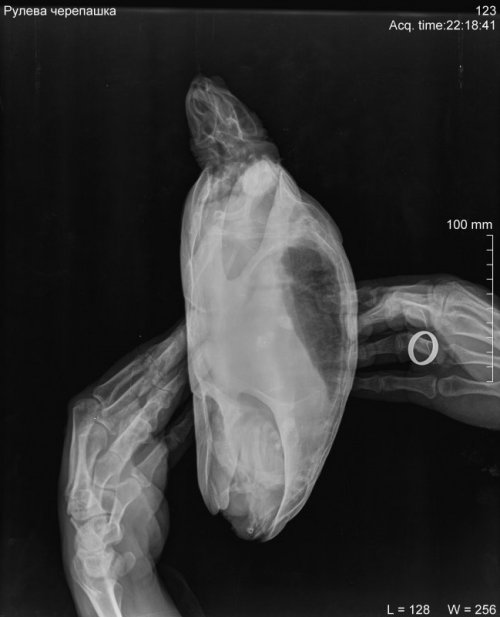

Podolnyi Ваше имя: Подольный Константин Локация: Украина, Днепр Опубликовано: 2 февраля 2020 Опубликовано: 2 февраля 2020 На рентгене просматриваются 3 контрастных конкремента, но мне не нравится характер их расположения. Нужно делать узд черепахи, через паховую ямку, для исключения фолликулярного стаза. Ибо на рентгене, как по мне, я вижу фолликулы на разных стадиях созревания. С большей долей вероятности, это петрификация(кальцинация) фолликулов. С правой стороны (возле таза) виден контрастный участок, я предполагаю это в устье яйцевода. Через клоаку пальпировали черепаху?

Podolnyi Ваше имя: Подольный Константин Локация: Украина, Днепр Опубликовано: 7 февраля 2020 Опубликовано: 7 февраля 2020 К примеру почему нужно очно смотреть такого рода проблемы. На фото представлен рентген черепахи и справой стороны компьютерная томография. На рентген видно, но крайне плохо, на кт, сами видите